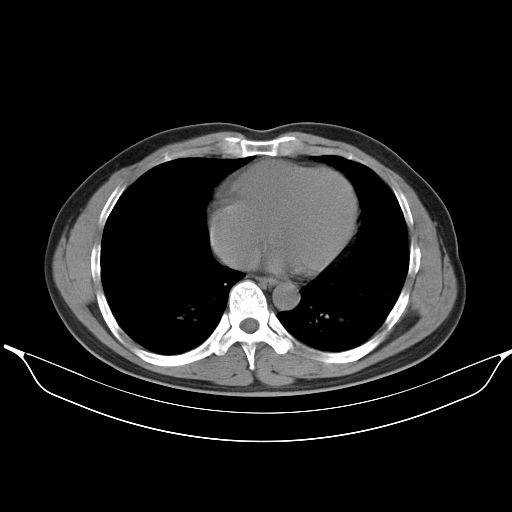

标题: CT25490:男,40岁,体检发现;无其它不适。 [打印本页]

标题: CT25490:男,40岁,体检发现;无其它不适。

考虑右下肺周围性肺癌并肺内多发转移,纵隔淋巴结转移!

支持 !考虑右下肺周围性肺癌并肺内多发转移,纵隔淋巴结转移,(气管前腔静脉后,隆突下,主动脉弓下都有了)

以下是引用wufeisheng在2010-4-1 23:09:00的发言:[br]考虑右下肺周围性肺癌并肺内多发转移,纵隔淋巴结转移!